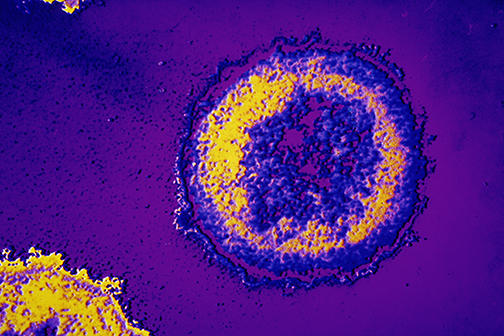

LSU Health New Orleans Precision Medicine Lab Finds New Omicron Subvariants

LSU Health New Orleans’ Precision Medicine Lab has found two new SARS-CoV-2 variants in Louisiana. BE.1 and BF.1 are subvariants of the Omicron Variant of Concern that has driven the latest surge. The Lab identified three cases of BE.1 and one case of BF.1 in tests performed at the end of June. More

LSU Health New Orleans Precision Medicine Lab Finds Omicron Variant

Among the 567 new COVID-19 cases reported today in Louisiana are two confirmed cases of the Omicron variant from the New Orleans area found by the LSU Health New Orleans’ Precision Medicine Laboratory. Directed by Lucio Miele, MD, PhD, Professor and Chair of Genetics at LSU Health New Orleans School of Medicine, along with Dr. Gordon Love, Professor and Chair of Pathology, the lab sequences samples from positive tests to learn what strains of the virus that causes COVID-19 are infecting patients here. More

1st Delta Variant Case Confirmed in Area

The Precision Medicine Lab at LSU Health New Orleans School of Medicine has identified the first Delta variant COVID case in Region 1 of Louisiana, which includes the New Orleans metropolitan area. More

LSU Health New Orleans Awarded $2.38M to Sequence COVID-19 Virus Variants

LSU Health New Orleans has been awarded $2.38 million in funding to lead partnerships to sequence SARS-CoV-2 variants. The funding is from a contract with the Louisiana Department of Health (LDH)) and a National Institute of General Medical Sciences supplement to the LACaTS (Louisiana Clinical & Translational Science Center) grant. More